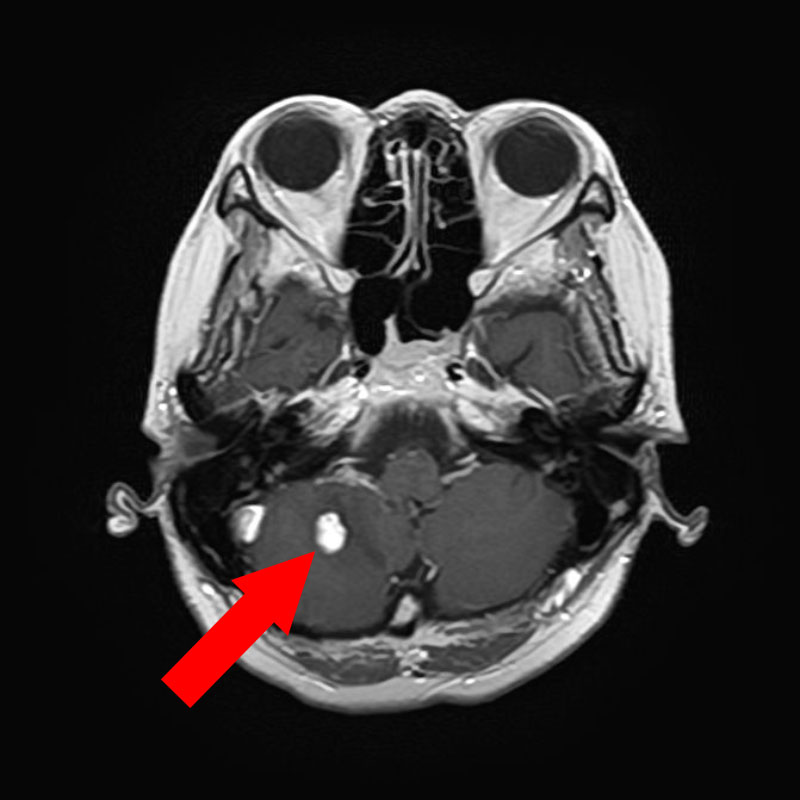

618

'25年4月

40代

小脳血管芽腫

頭蓋内腫瘍摘出術

No.’25_20 手術前1

No.’25_20 手術前2